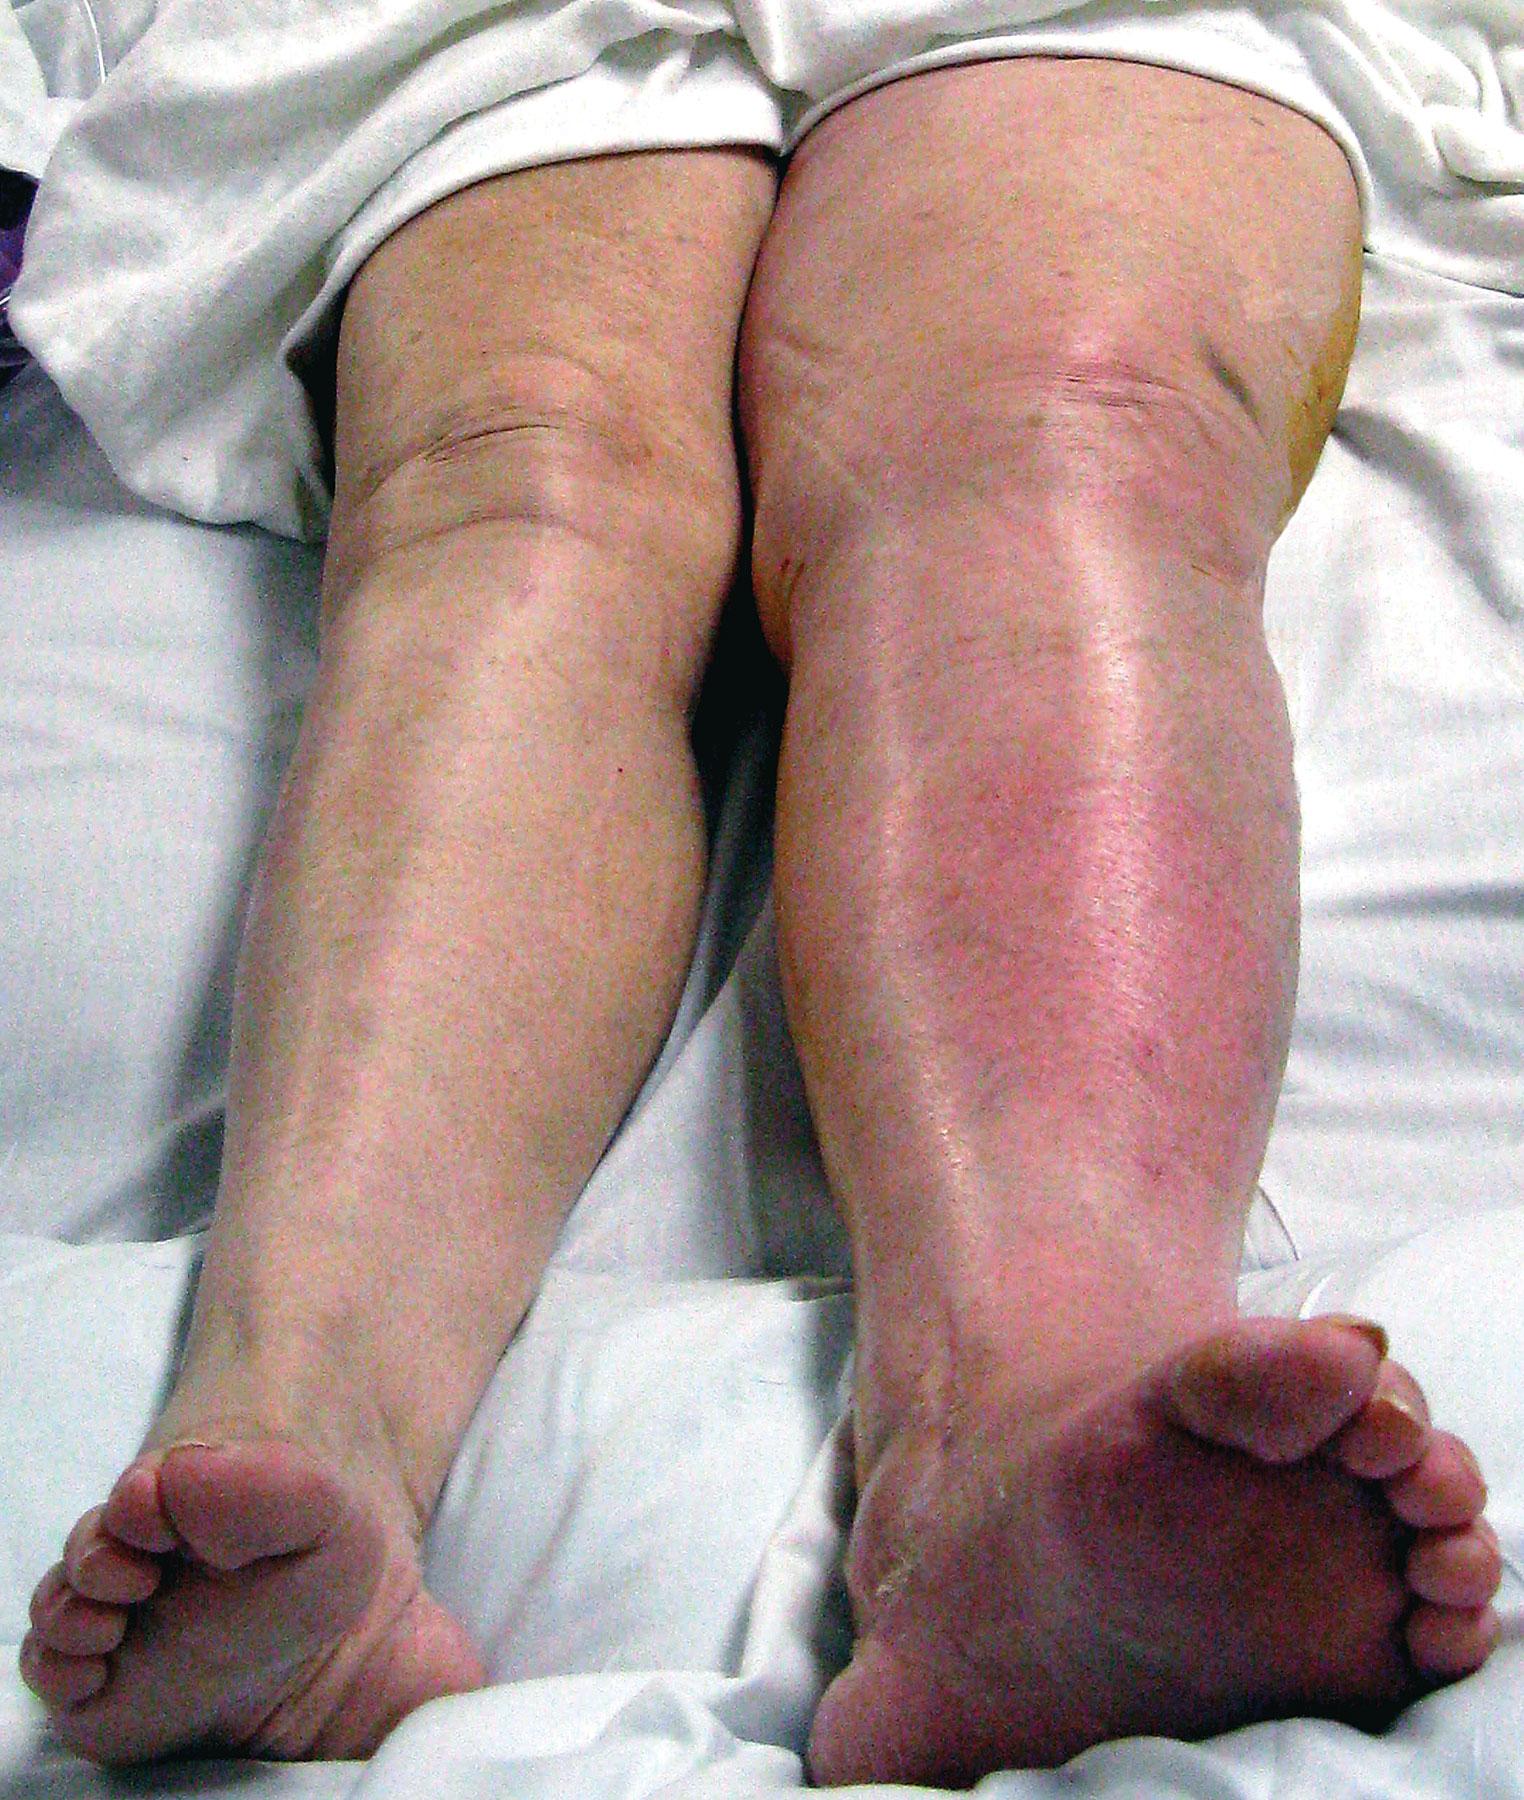

علائم ترومبوز ورید عمقی (DVT)

DVT ممکن است بی‌علامت باشد، اما در صورت بروز علائم، معمولاً شامل موارد زیر است:

• تورم ناگهانی یک پا (معمولاً یک‌طرفه)

• درد، سنگینی یا گرفتگی پا

• قرمزی یا تغییر رنگ پوست

• گرمی ناحیه درگیر

• حساسیت به لمس

• برجسته شدن وریدهای سطحی

⚠️ تورم و درد یک‌طرفه پا همیشه باید جدی گرفته شود.